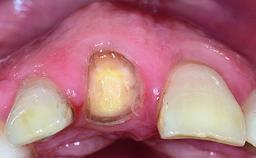

A 30-year-old patient presented at our clinic with a chief complaint of pain in her endodontically treated right maxillary central incisor (tooth 11) with a post-and-core and a fixed single crown. She had a very high lip line, a medium to thin soft-tissue phenotype, and a medium scalloped gingival contour. She also had high esthetic expectations because of her young age and beautiful smile. However, her expectations were realistic and she understood the risks of the treatment. At the initial clinical examination there was a slight mobility of tooth 11; no fistula was observed. The patient also had a single crown on the adjacent tooth 21. Both restorations were old and esthetically deficient. A digital periapical radiograph showed a very small periapical radiolucency, a thick intraradicular post, and no separation between root fragments.